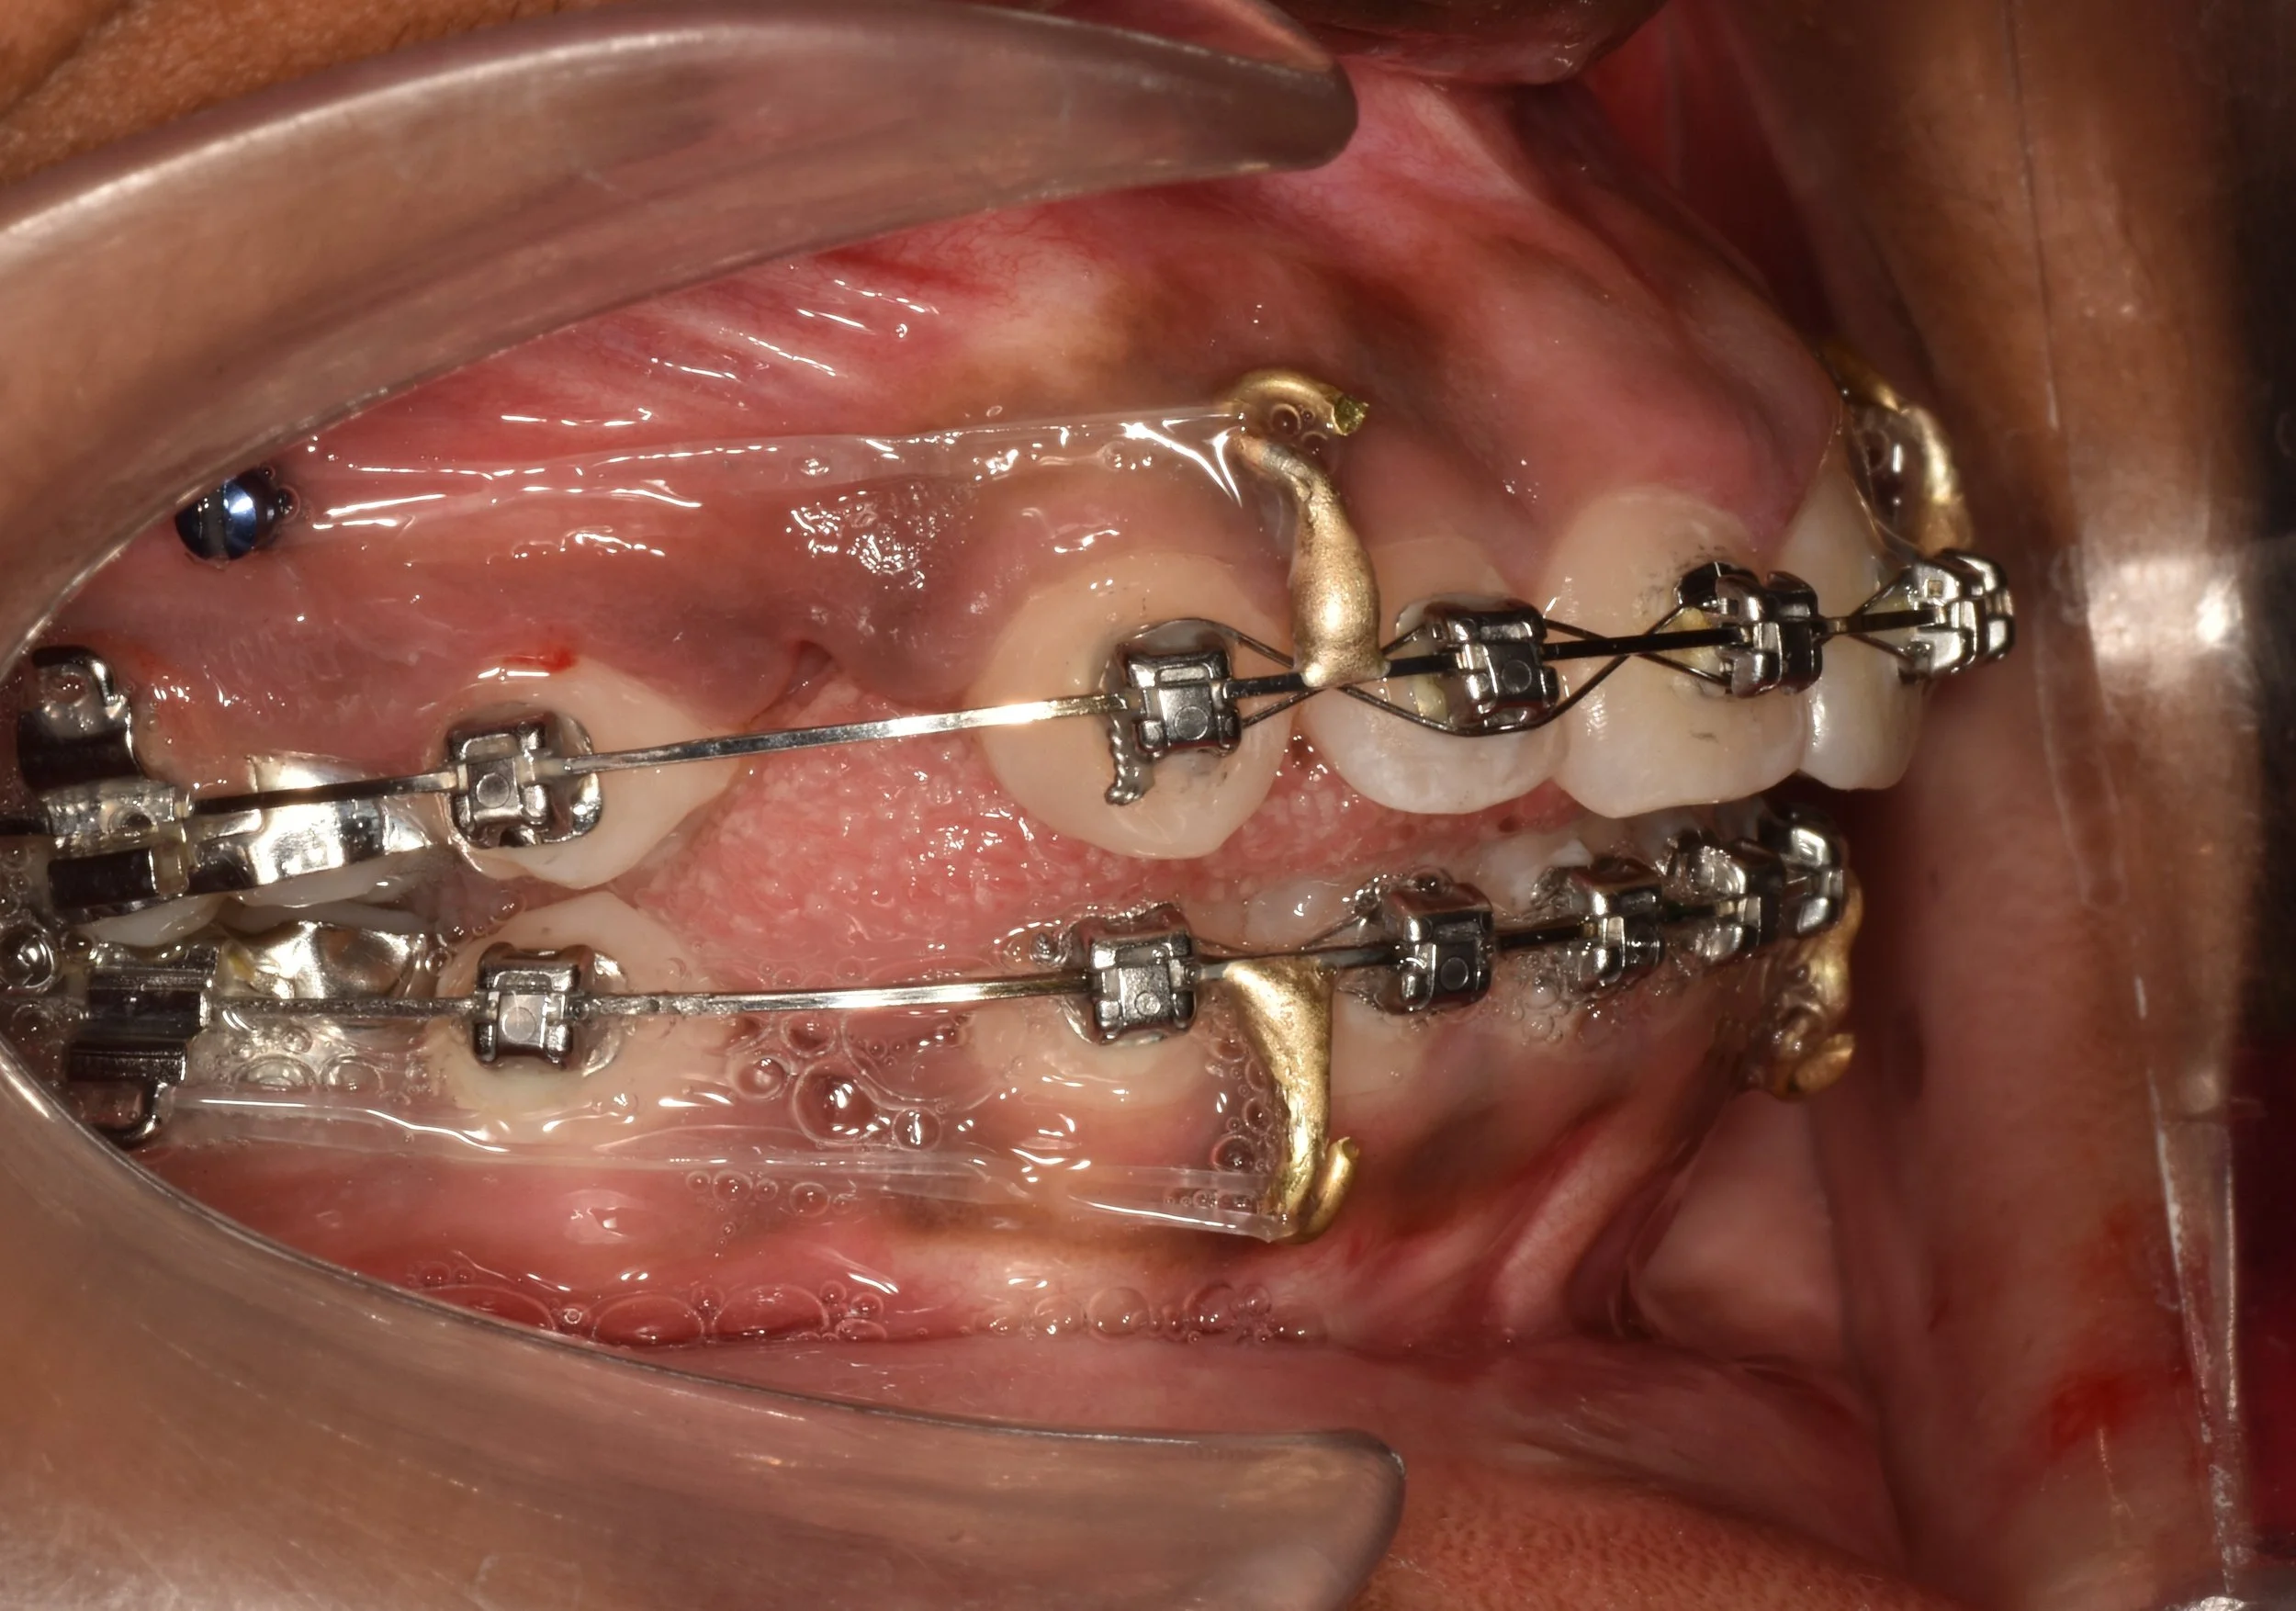

Extra-radicular implants